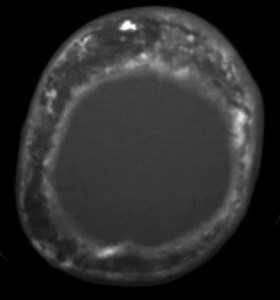

Corte axial de TC de cráneo del mismo paciente, visto en ventana de hueso, que muestra el marcado engrosamiento del hueso y el aspecto algodonoso.